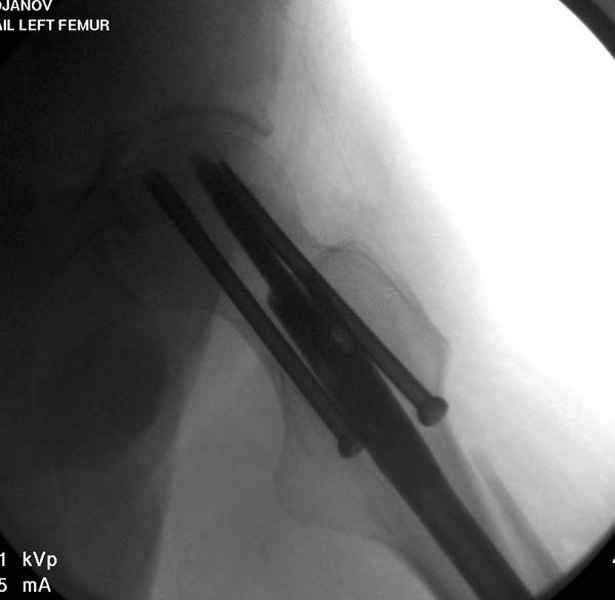

Среди русскоговорящих коллег Ортофорум стал одним из мест, где многие из нас черпают знания для решения своих ежедневных проблем в виде практических советов и обмена опытом. Кроме таких советов, Ортофорум стал источником новых познаний среди ортопедов, особенно по редко встречающимся состояниям в ортопедии. Продолжая традицию, я хотел бы представить редко встречающий случай перелома бедра у больного с гемофилией. Больному 42, гемофилия типа А, из истории упал с высоты около 1,5 метра, переправлен из другой больницы. По происхождению мексиканец, 10 лет назад по поводу артроза пр. коленного сустава в Мексике сделано протезирование, которое закончилось ампутацией выше коленного сустава. При поступлении бедро напряженное, сосудистых и неврологических расстройств нет. На рентгенограмме оскольчатый перелом бедра с вовлечением проксимальной спирали в шейку бедра. Хотели бы знать тактику ведения подобных больных и на что надо обратить внимание? Djoldas Kuldjanov, MD Department of Orthopedic Surgery St. Louis University Medical Center

Учитывая, что случай ургентный, больной поступил вечером, не стали делать вытяжение и срочно провели операцию по фиксации перелома бедра антеградным штифтом Versa Nail от DePuy.

Для профилактики дальнейшего раскола в шейке предварительно во время проксимального рассверливания спереди и сзади провели временные спицы, которые в дальнейшем были заменены на шурупы (miss nail method)